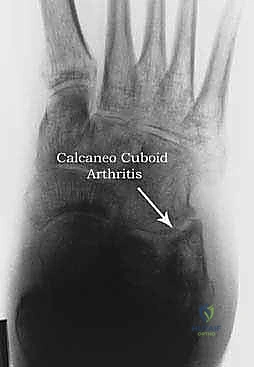

6. التهاب المفصل العقباني النردي (Calcaneocuboid Arthritis)

في بعض الأنماط المعقدة من الكسور، يمتد خط الكسر إلى الجزء الأمامي من عظم العقب ليصيب المفصل العقباني النردي. سوء الالتئام هنا يؤدي إلى التهاب مفصلي إضافي في منتصف القدم، مما يضيف طبقة أخرى من الألم ويتطلب في بعض الأحيان تثبيتاً جراحياً ممتداً يشمل هذا المفصل أيضاً.